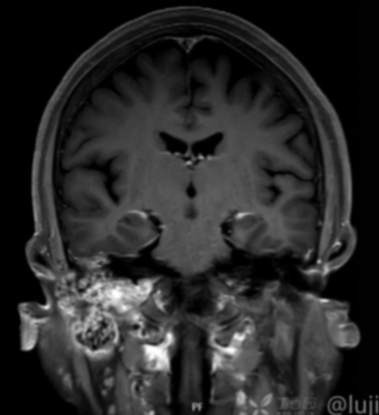

(2023-05-15 10:00,本院)行磁共振(颅脑)检查提示:右侧乳突区异常信号,考虑恶性、软骨来源肿瘤,软骨肉瘤可能性大。(集体讨论意见);脑内散在多发缺血灶。

(2023-05-12 10:15,本院)行CT(颅脑)检查提示:右侧颞骨广泛骨质破坏,伴巨大软组织肿块,性质待定,考虑肿瘤性病变,颈静脉球瘤?软骨源性肿瘤?请结合临床及病理进一步明确。